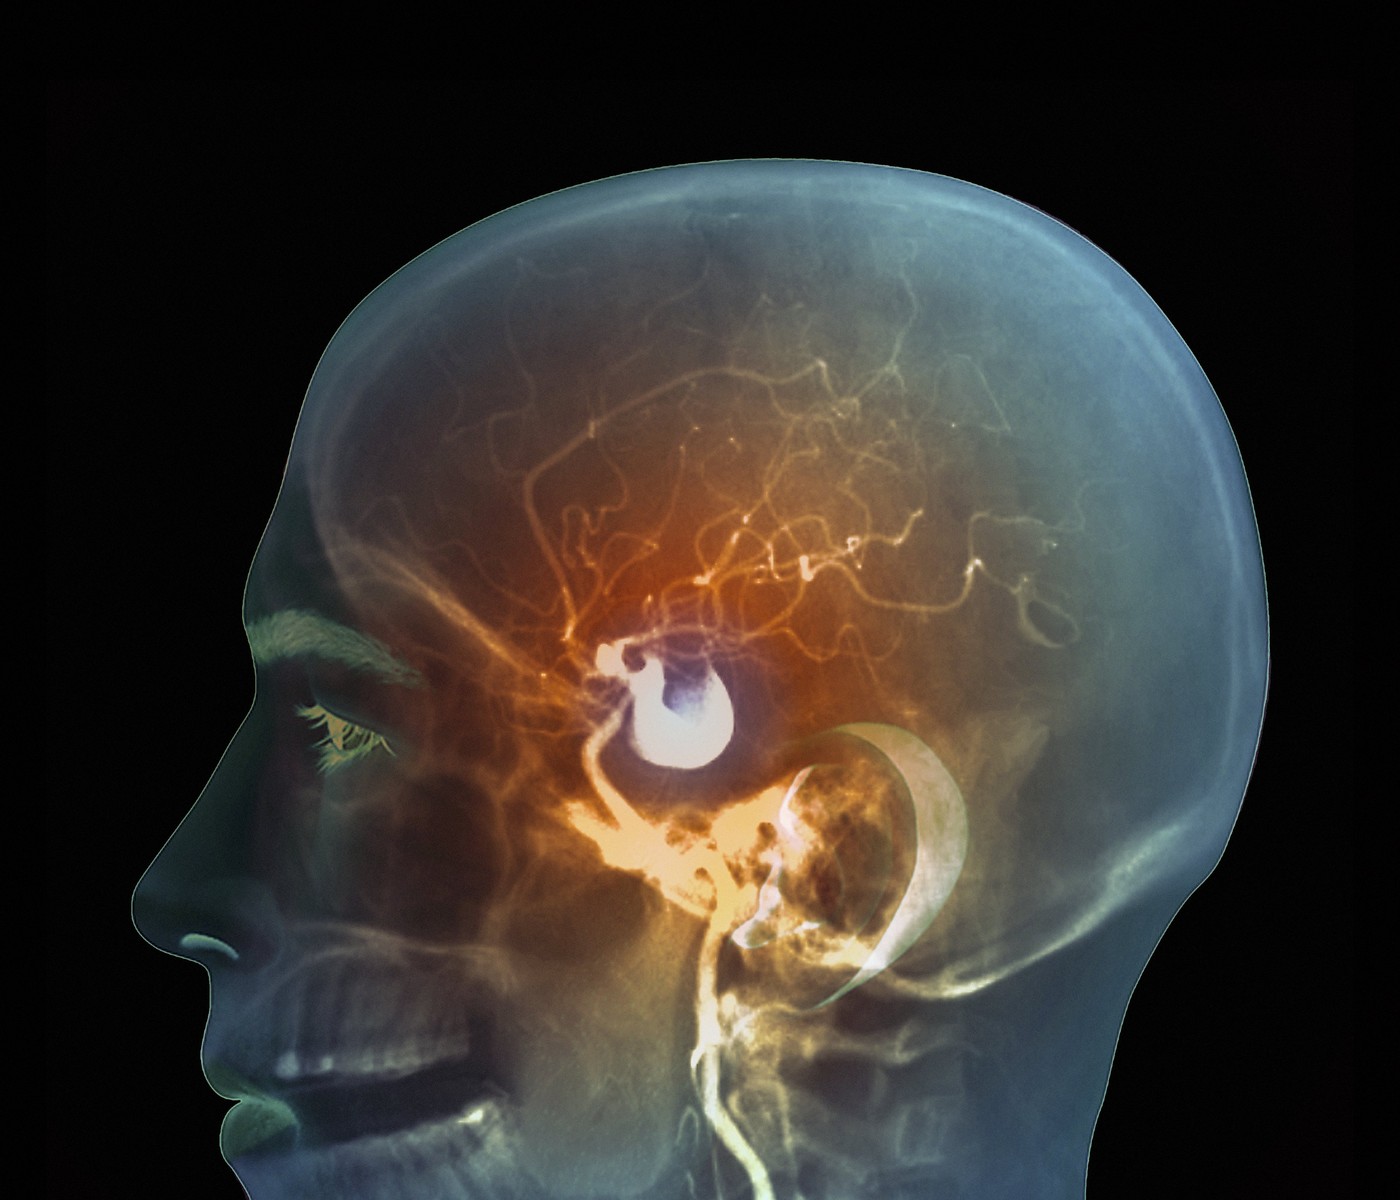

Aneurizma u mozgu; Foto: ZEPHYR / Sciencephoto / Profimedia Aneurizma u mozgu; Foto: ZEPHYR / Sciencephoto / Profimedia Aneurizma u mozgu; Foto: ZEPHYR / Sciencephoto / Profimedia Kako da znaš da imaš aneurizmu u mozgu koja samo čeka da eksplodira: Ovo je simptom koji mnogi osete, a misle da nije ništa ozbiljno autor: Nova.rs Zdravlje 06. feb. 2025. 07:20 1 Podeli vest: Aneurizma u mozgu je ozbiljno stanje koje ponekad može da prođe potpuno nezapaženo dok ne dođe do iznenadne, potencijalno smrtonosne rupture. Podeli vest: Oglas Aneurizma se javlja kada se deo zida arterije, krvnog suda, izduži i stvori izbočinu. Iako se može desiti u bilo kojem krvnom sudu, najčešće je prisutna u arterijama mozga i aorti (velikoj arteriji koja izlazi iz srca). Kako nastaje aneurizma u mozgu? Zidovi arterija moraju biti čvrsti da bi podneli stalni pritisak krvi koja protiče kroz njih. Aneurizma nastaje kada postoji slaba tačka na tom zidu, što može biti uzrokovano različitim faktorima. Arterijski zidovi se sastoje iz tri sloja: unutrašnji sloj od ćelija, srednji sloj sa mišićima i elastičnim vlaknima, i spoljašnji sloj sa kolagenom. Oštećenje bilo kog od ovih slojeva dovodi do toga da zid arterije postane tanak, istegne se i formira izbočinu. Genetika i određeni nasleđeni poremećaji mogu oslabiti arterijske zidove, a proces starenja takođe povećava rizik. Prosečna starost kada se aneurizma otkrije je oko 50 godina. Žene su pod većim rizikom od aneurizme nakon 50. godine, jer opadanje estrogena smanjuje količinu kolagena u arterijskom zidu, čineći ga slabijim, napominje Science alert. Simptomi koje ne treba ignorisati Mnogi ljudi imaju aneurizmu u mozgu i nisu ni svesni toga. Američka Nacionalna biblioteka medicine navodi da troje od 100 ljudi ima moždanu aneurizmu, veličine od manje od 5 mm do više od 25 mm u prečniku, ali se većina otkriva samo tokom snimanja radi nekog drugog problema (na primer, traume glave). Manje aneurizme možda neće izazvati nikakve simptome, dok veće mogu pritiskati mozak i živce, što izaziva glavobolje, mučninu ili poremećaj vida. Ako osećate česte glavobolje, posebno ako su povezane sa osetljivošću ili nelagodnostima u određenom delu glave, to može biti signal da postoji mali „curenje“ krvi iz aneurizme, što povećava rizik od njenog pucanja u narednim danima ili nedeljama. Nažalost, mnogi ljudi te simptome doživljavaju kao obično umor ili stres, ne shvatajući ozbiljnost stanja. Klasičan simptom koji mnogi opisuju je „gromoglasna glavobolja“ koja je nagla i vrlo jaka, a često je praćena i problemima sa vidom, gubitkom pokreta, mučninom i gubitkom svesti, što može ukazivati na pucanje aneurizme. Ukoliko aneurizma u mozgu doživi rupturu, to može dovesti do subarahnoidnog krvarenja, što je ozbiljna vrsta moždanog udara. Samo 1 od 100 aneurizmi zapravo pukne, ali ukoliko dođe do rupture, više od 25% ljudi umre u prvih 24 časa, a više od 50% premine u naredna tri meseca. Faktori rizika: šta povećava šanse za aneurizmu? Iako se aneurizma može javiti bez očiglednog uzroka, postoje faktori koji povećavaju rizik. Visok krvni pritisak, pušenje, zloupotreba kokaina, stres i visok unos alkohola mogu svi doprineti slabljenu arterijskih zidova i povećanom riziku od aneurizme. Osobe sa problemima sa holesterolom, gojaznošću ili visokim krvnim pritiskom takođe su u većem riziku. Aneurizme koje su veće od 7mm obično zahtevaju hirurški zahvat, jer se kod manjih aneurizmi rizik od rupture smatra manjim. Rizik možete smanjiti zdravim životnim navikama. Prestanak pušenja, umerena konzumacija alkohola, zdrav režim ishrane, fizička aktivnost i kontrola telesne mase mogu vam pomoći da očuvate snagu vaših arterija i smanjite rizik od aneurizme. Ako sumnjate na simptome koji bi mogli ukazivati na aneurizmu, posetite lekara i obavite potrebne testove. "Imam rak pluća i ovaj simptom me je užasno nervirao, a nisam znao da je to znak da sam teško bolestan" Zdravlje 1 Ovo je najčešći kancer u Srbiji: Pogledajte spisak svih simptoma koji se osete pre dijagnoze Zdravlje 4 Evo kad je kamen u žuči opasan i operacija je jedino rešenje: Često nema simptoma, ali jedna stvar se odmah primeti Zdravlje 1 Bio je "potpuno zdrav" i samo jedan simptom je osetio pre nego što su mu saopštili da "ima još samo nekoliko meseci života" Zdravlje 1 aneurizma aneurizma mozga arterije simptomi Pratite nas na društvenim mrežama: Koje je tvoje mišljenje o ovoj temi? Učestvuj u diskusiji ili pročitaj komentare Budite prvi koji će ostaviti komentar Pošalji komentar Pročitaj komentare (1)